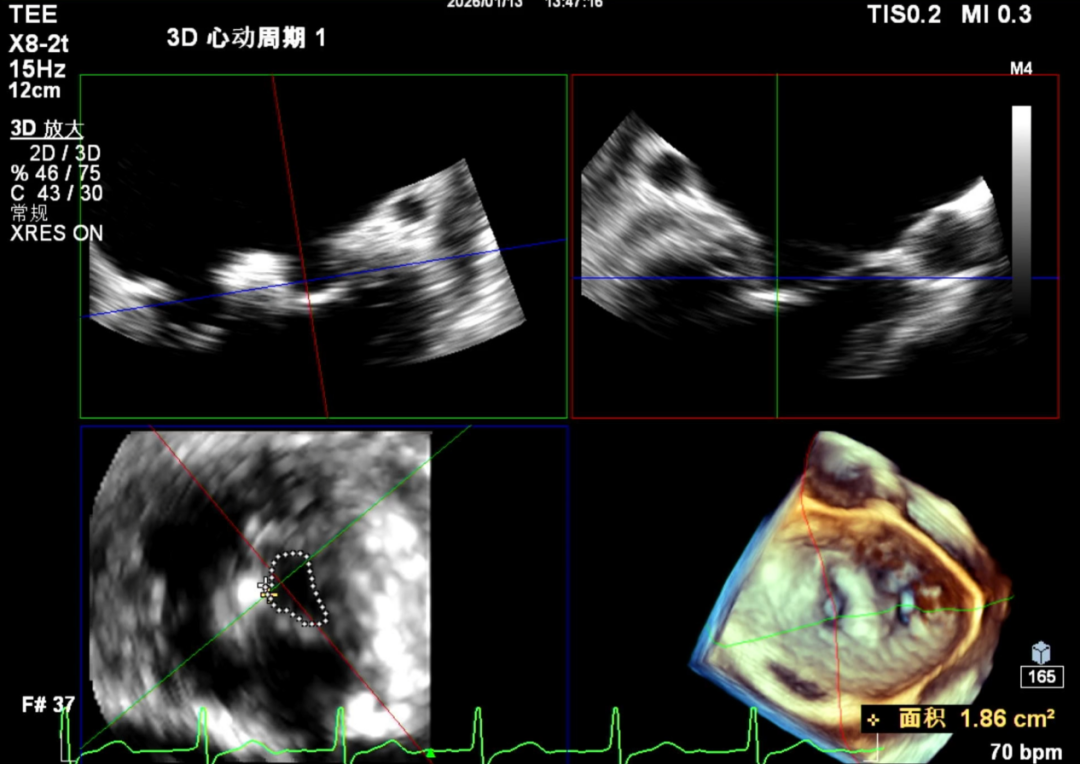

3D

怎么上穿刺鞘攻克巨大左房伴转位穿刺难关!温医大附一院周浩教授团队创新应用“导丝定位+可调弯鞘”技术完成高难度TEER手术_https://www.jmylbn.com_新闻资讯_第9张

1.二尖瓣重度关闭不全(4+),瓣环明显扩大(AP径4.6cm,LM径3.9cm),扁平,关闭时瓣叶对合不佳(carpentier I),1-3区均可见反流束,返流宽度达26mm;肺静脉频谱呈收缩期反向。

2.画迹法测得二尖瓣瓣口面积约8.8cm²。

5.左房巨大(三径86*84*114mm),右房巨大(内径114*86mm),CFI提示极重度三尖瓣反流,Teich法测得EF为70.1%。